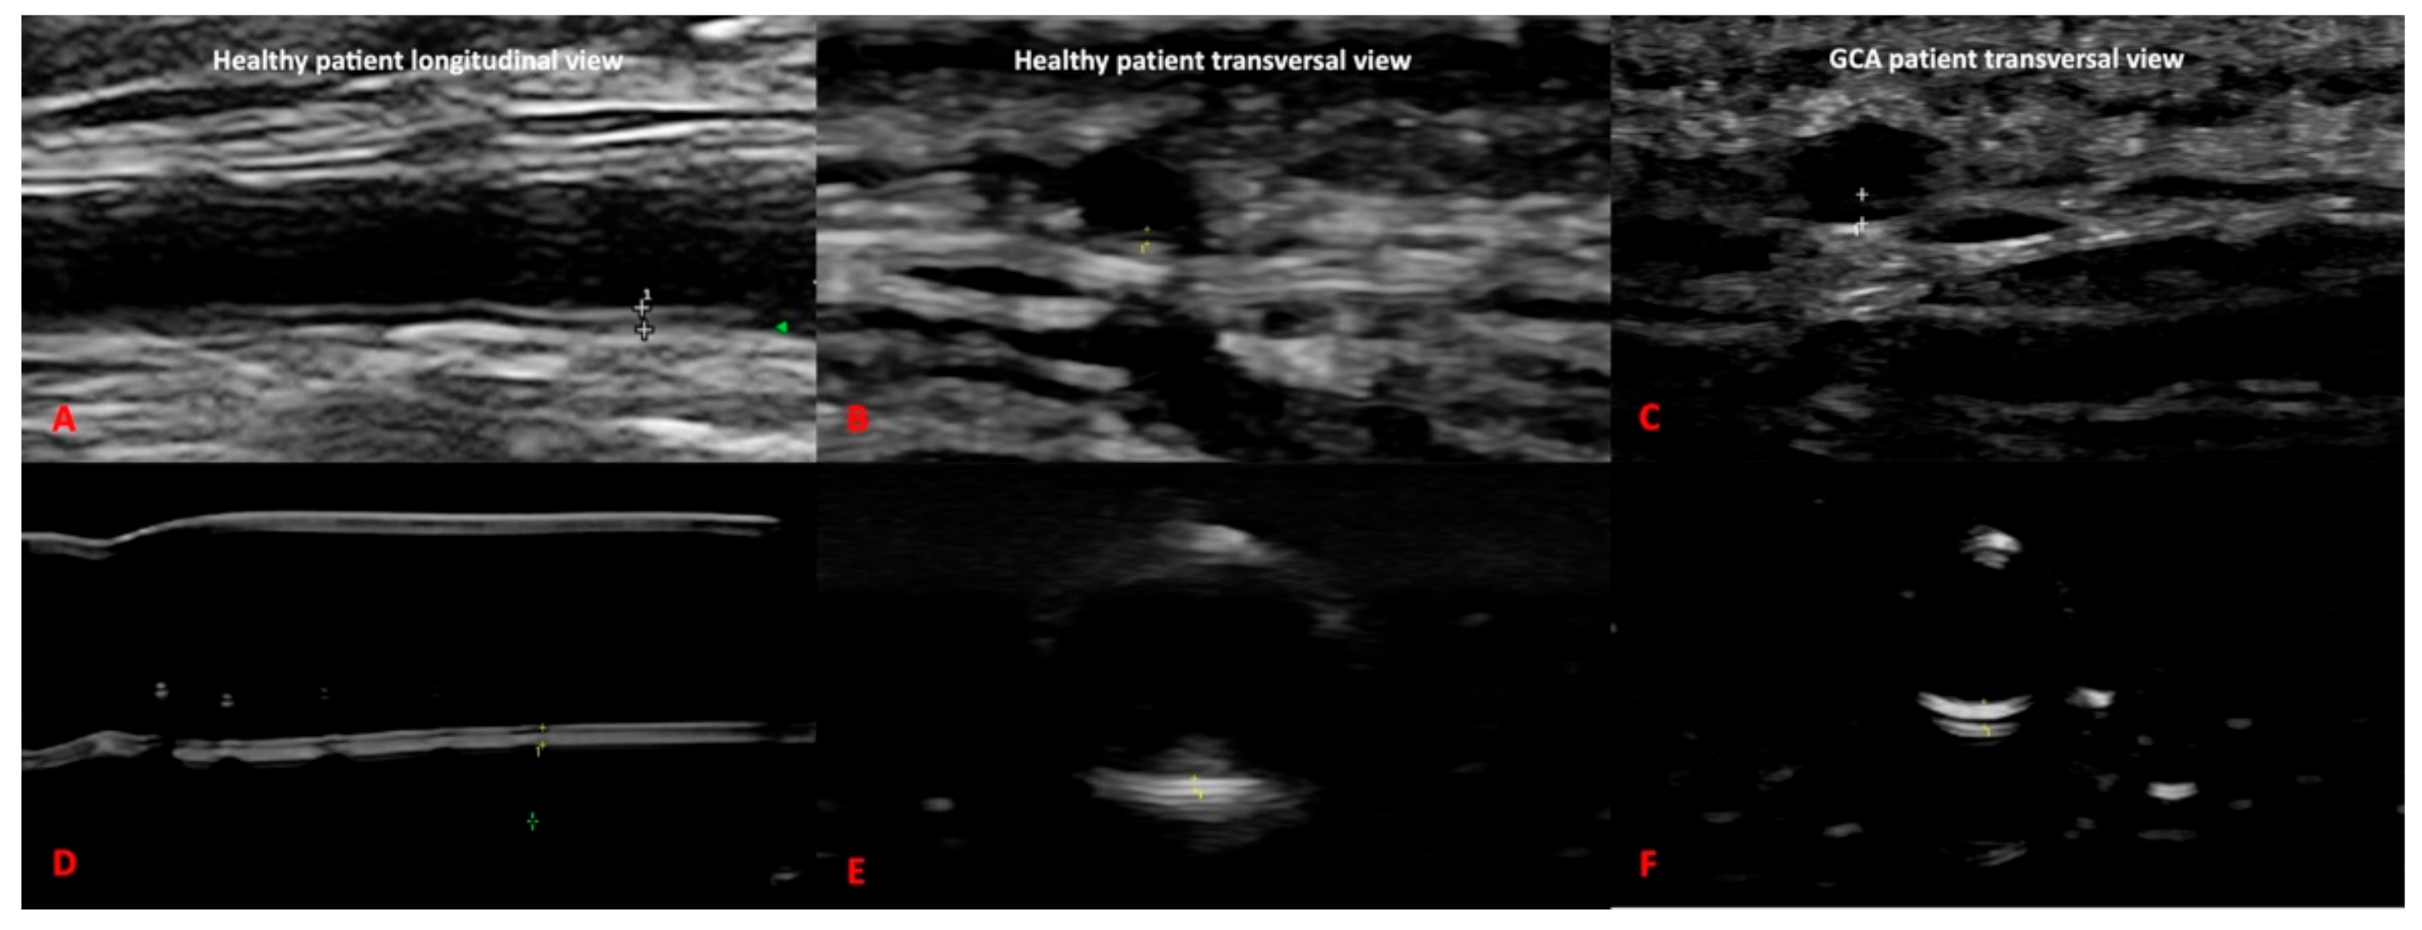

Our 3D printed artery models fulfilled the OMERACT definitions of normal and pathological temporal and axillary arteries in GCA [5] (Figure 4 and Figure 5). In addition, we were able to replicate the IMT of the corresponding arteries, allowing the measurement of the IMT values of the normal and pathological arteries. These values corresponded to the published cut-off values [20,21,22] for ultrasound diagnosis in GCA of the temporal or axillary arteries.

Figure 4. Comparison between ultrasound images of the axillary artery of the 3D printed models (C,D) and real ultrasound images in healthy and giant cell arteritis patients (A,B).

Figure 5. Comparison between ultrasound images of the temporal artery of the 3D printed models of healthy (D,E) and pathological setting (F) and real ultrasound images in healthy (A,B) and giant cell arteritis patients (C).